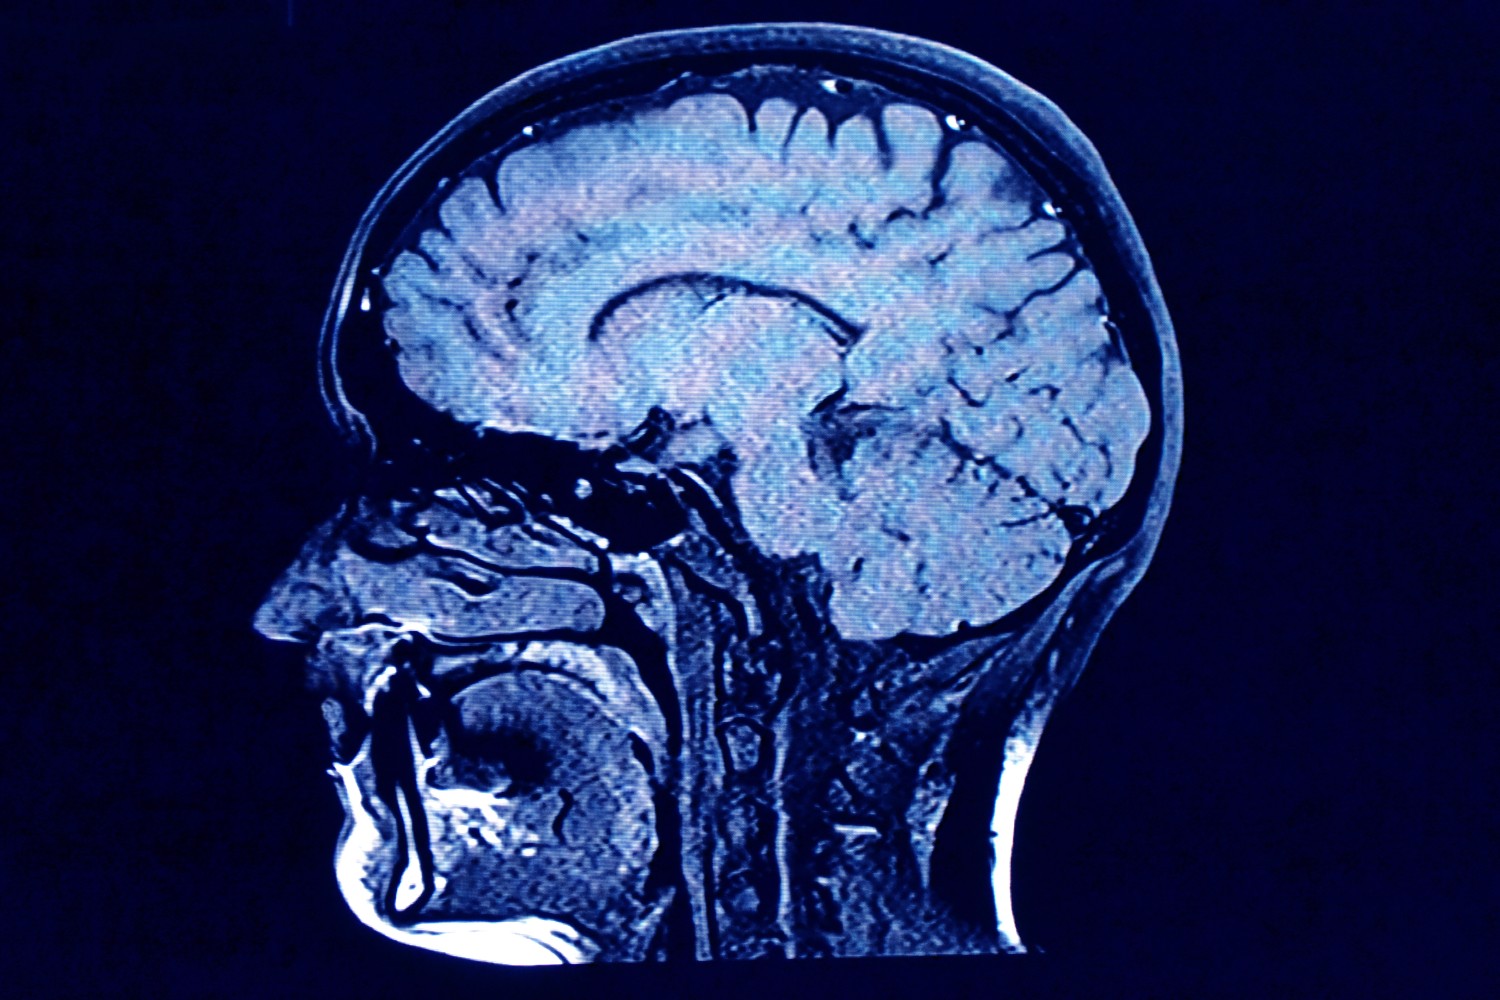

Brain scan

A new study sheds more light on how the brain ages.

Getty Images